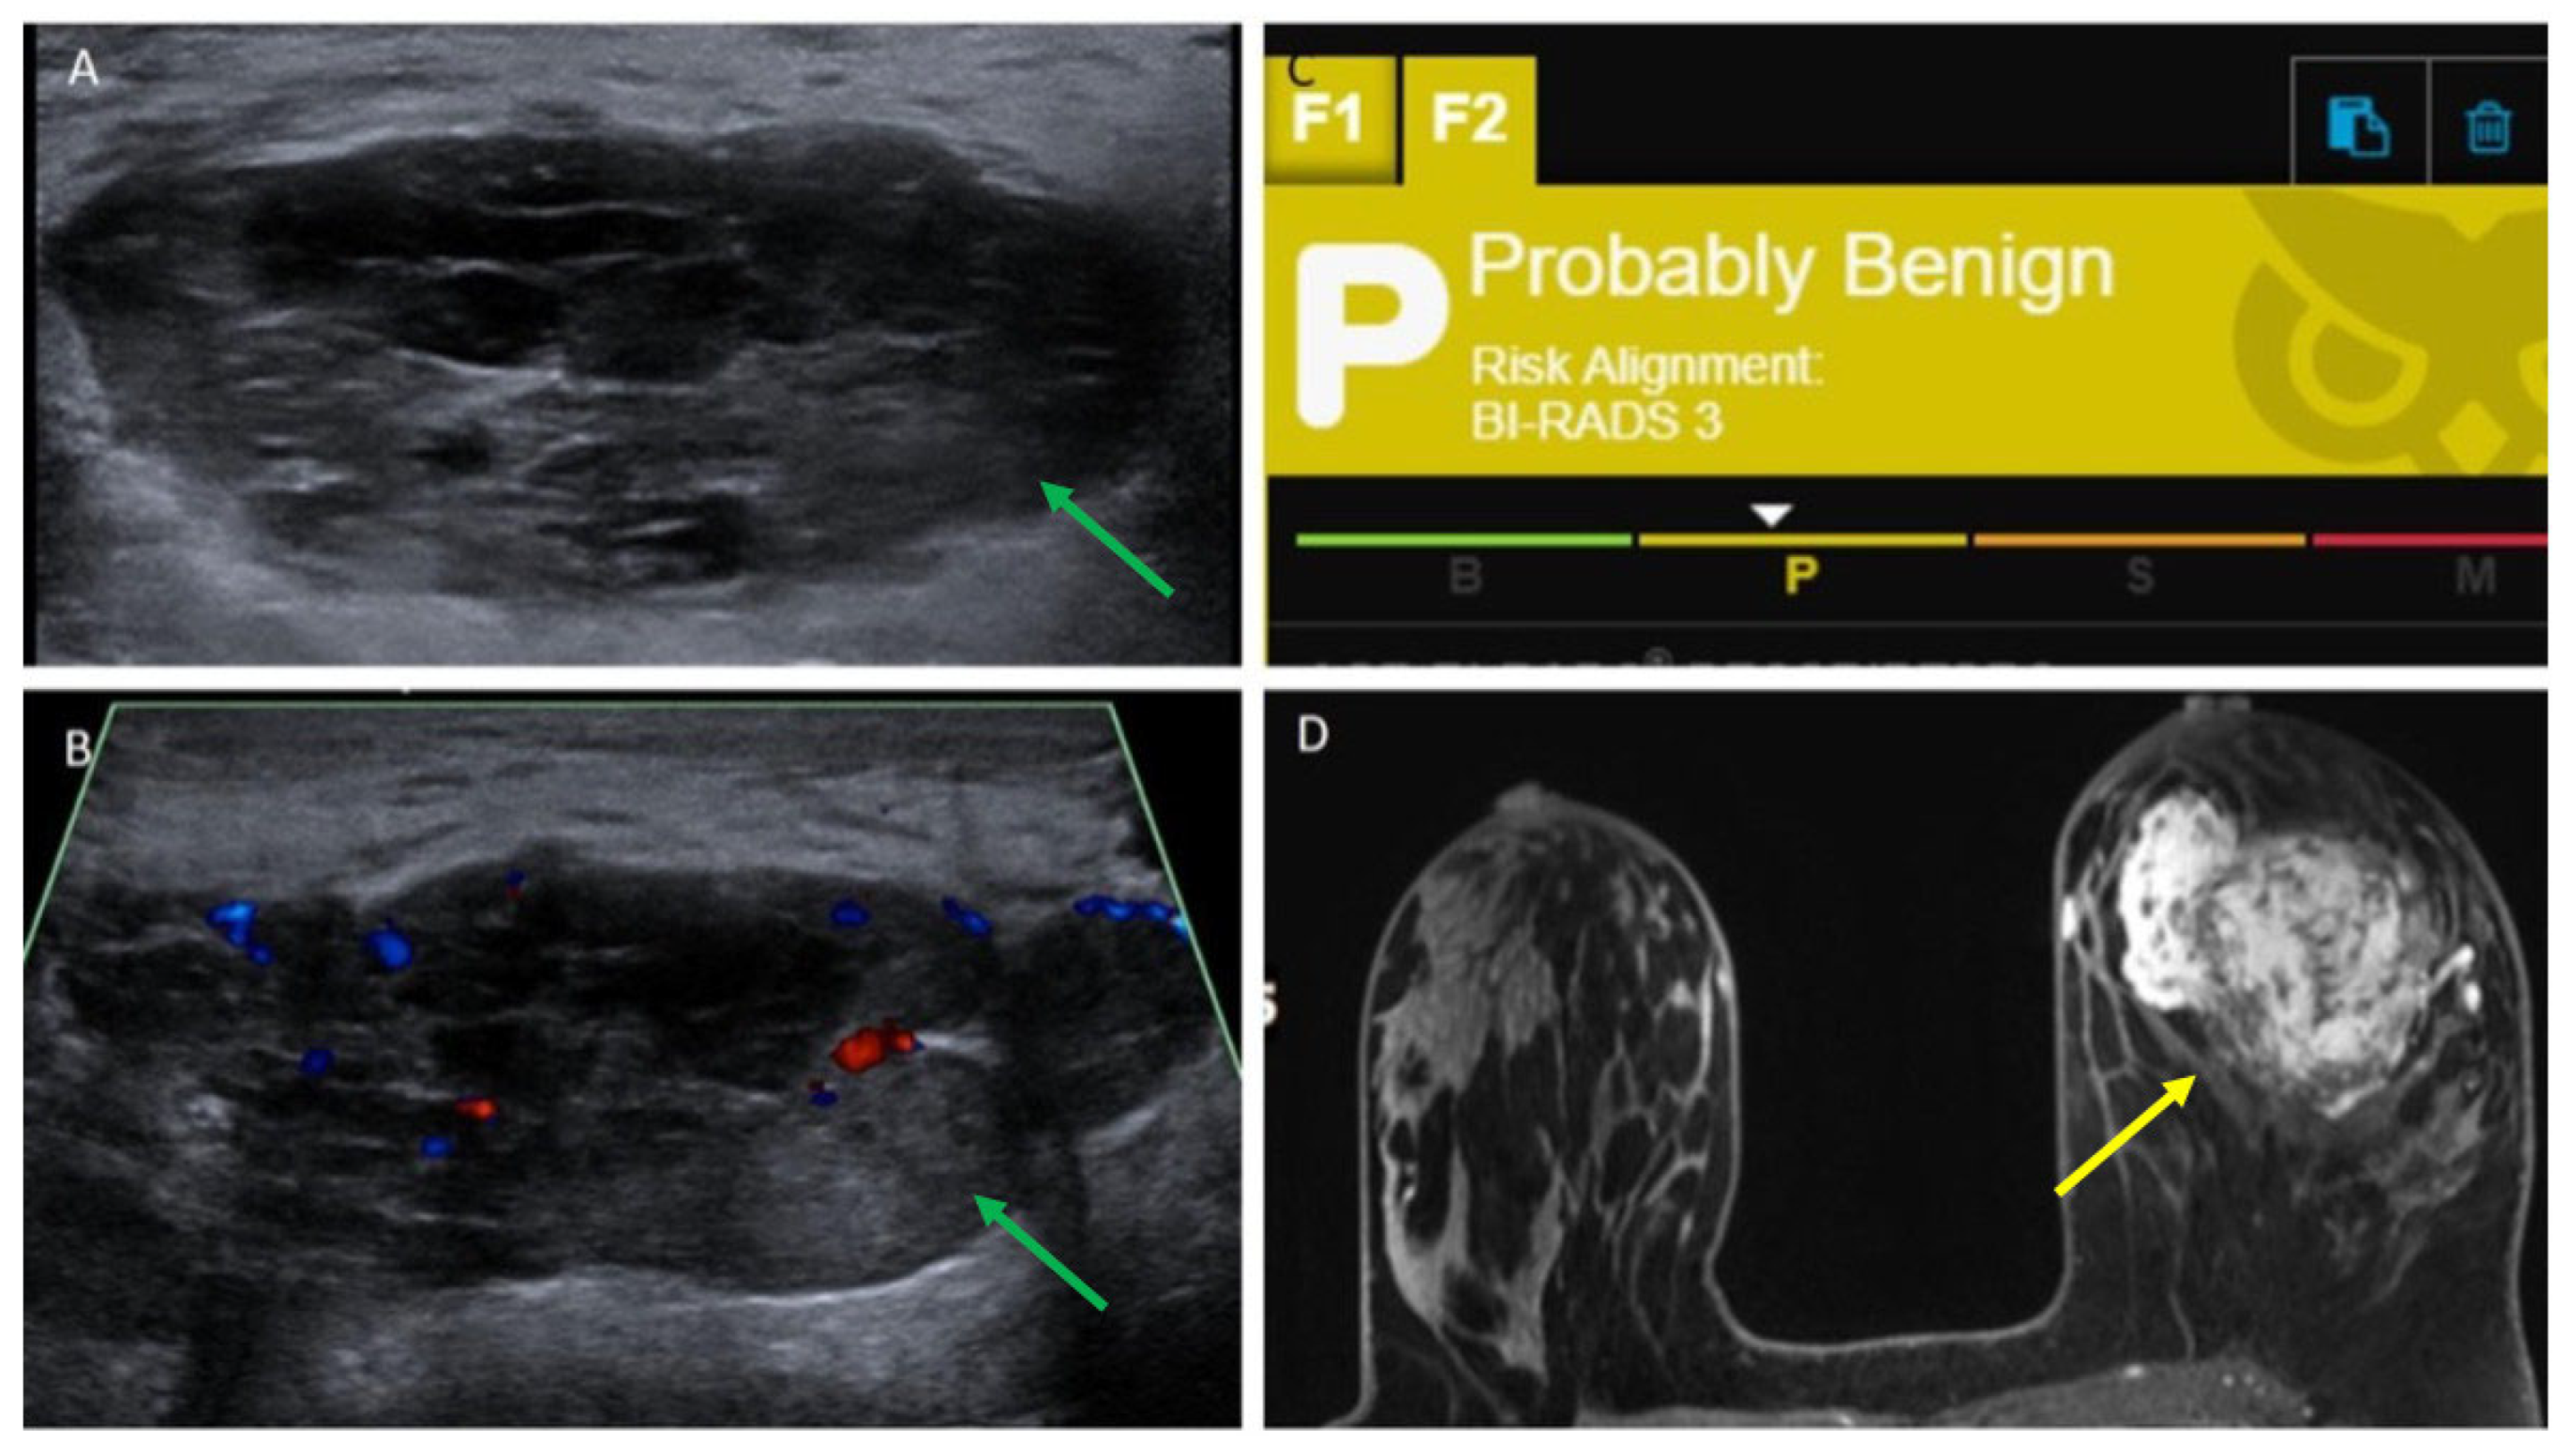

| 16 | 5.5 | Ultrasound core needle biopsy | Irregular, equal-density mass with indistinct margins | Oval, parallel, hypoechoic mass with obscured margins, posterior acoustic enhancement and Doppler flow | Probably Benign, 3 | Irregular mass with irregular margins and heterogeneous enhancement |

3.5. AI Analysis

4. Discussion